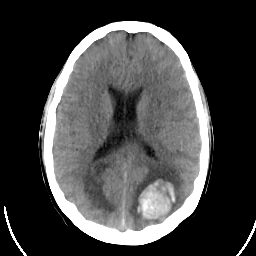

Sarcoma: Roentgen-ray CT -- Slice #14

[Home][Help][Clinical] Slice 14